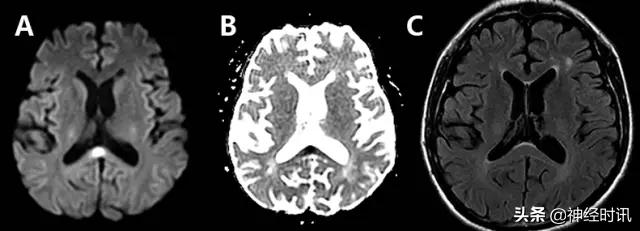

多发性硬化

多发性硬化可因突发性局灶性神经功能障碍(如失语或偏瘫)而就诊。其典型MRI表现为脑室周围白质、深部白质和皮质旁出现T2高信号病灶。急性病变通常伴有弥散增加,但其偶尔可能会显示为一过性(2~7天)弥散受限(图20)。弥散受限通常见于病变的边缘,但也可能是中心性的。这些病变大多伴有与亚急性卒中类似增强现象,提示为活动性炎症。少突胶质细胞、髓鞘和轴突等由于兴奋性毒性损伤所致的细胞毒性水肿,可能是此类患者发生弥散受限的原因。

图20 一例21岁女性复发-缓解型MS患者,17岁时为评估其轻微脑震荡综合征而进行的首次MRI检查偶然发现多发性硬化。其表现为:幕上存在以特征性模式分布的多发性T2高信号病灶(C:FLAIR),且右额叶白质存在一个弥散受限病变(A:DWI,B:ADC)。